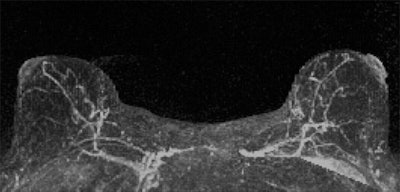

Contrast enhancement of normal tissue on breast MRI scans is more effective than tissue density as an imaging biomarker of breast cancer and could make existing risk models more accurate, according to a new study published online May 12 in Radiology.

Researchers from the University of Washington found that women with an MRI assessment of mild, moderate, or marked background parenchymal enhancement (BPE) were nine times more likely to develop breast cancer than women with minimal BPE. In contrast, tissue density measured by both MR and mammography was not a statistically significant indicator.

So Dontchos' group decided to explore imaging markers that could improve breast cancer risk assessment, investigating whether there were any associations between breast cancer risk and imaging features such as BPE, the amount of fibroglandular tissue (FGT) on MR, and breast tissue density.

BPE, however, was significantly linked to cancer: The women with mild, moderate, or marked background parenchymal enhancement made up the majority of the cancer cohort.

"We found that a significantly higher percentage of women in the cancer cohort had either mild, moderate, or marked BPE (78%) than did women in the control cohort (43%)," the authors wrote.